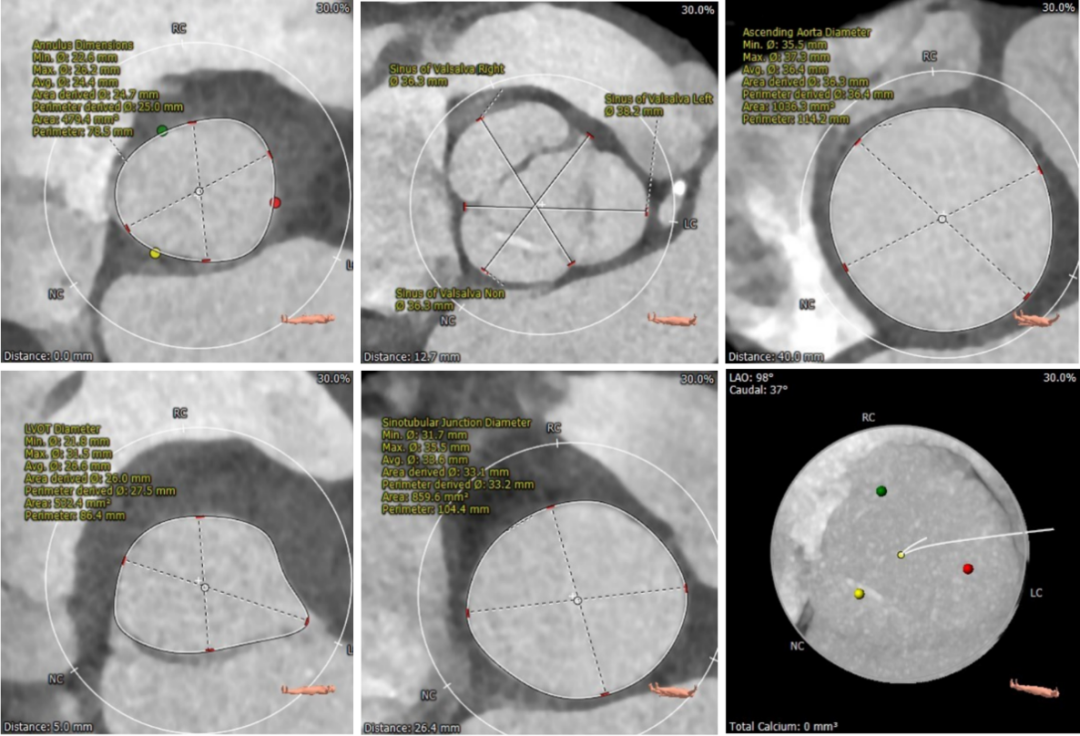

术前CT评估

▪ 三叶式主动脉瓣,微量钙化,瓣叶稍增厚。

▪ 左右冠高度可,左右冠瓣长度小于冠脉开口与瓣叶附着缘距离。

▪ 左室流出道呈直筒型,瓣环下4cm流出道内径约26mm,瓣环下5mm内径约27.5mm,稍大于瓣环内径。瓦氏窦较宽,窦管交界及升主动脉内径可,升主动脉无扩张。

▪ 左室腔内径可,心室壁无增厚。

▪ 主动脉瓣环与水平面夹角较大61°,横位心,主动脉弓角度较锐利76°,弓距良好。

主动脉根部测量及钙化评估

冠脉阻挡风险评估